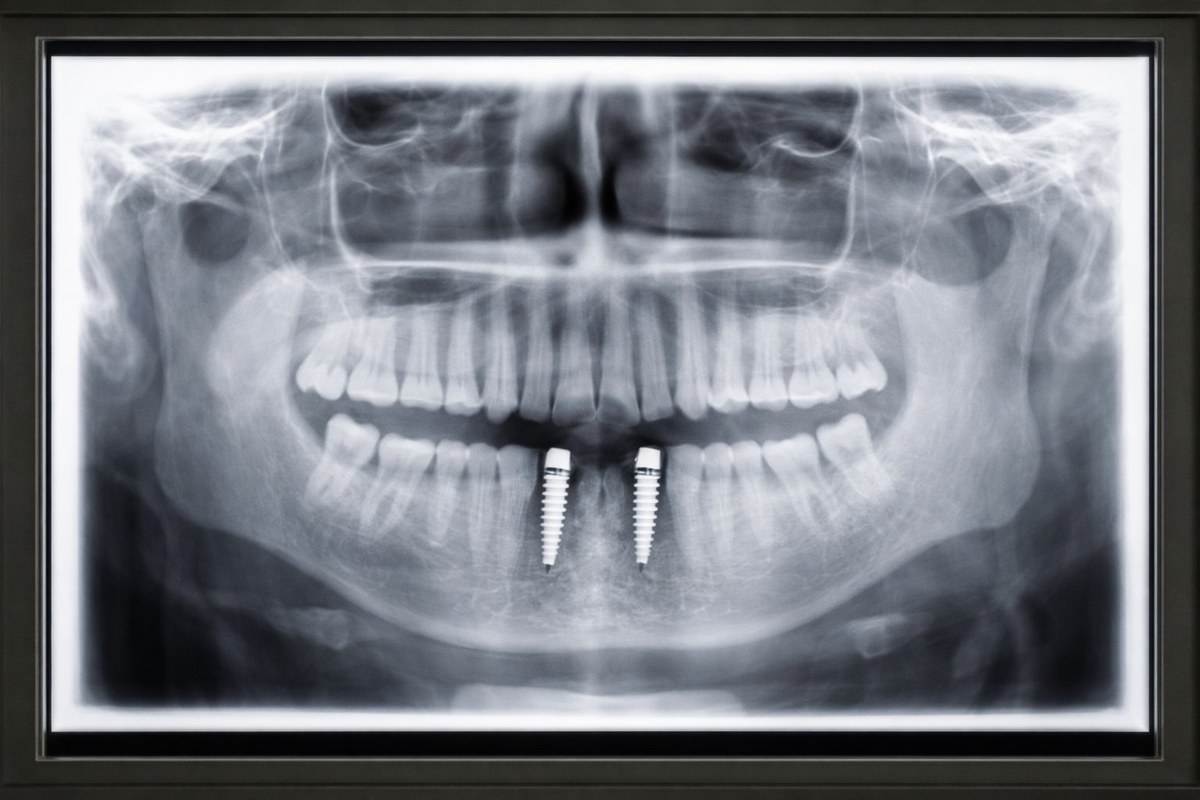

כשאומרים שאין מספיק עצם, הכוונה בדרך כלל לכך שחסר גובה, רוחב או שניהם, כך שלא ניתן להחדיר שתל בצורה בטוחה ויציבה במיקום המתוכנן. זה נפוץ אחרי שנים בלי שיניים, אחרי מחלת חניכיים, טראומה, עקירות ישנות או תותבות שלחצו

על הרכס לאורך זמן. אבל "אין עצם" הוא לא אבחנה אחת. יש הבדל גדול בין מחסור קל ומקומי לבין ספיגה נרחבת של לסת שלמה.